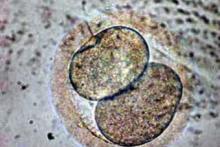

Izolace kmenových buněk z tukové tkáně (adipose-derived stem cells, ASCs), které mohou dát vznik buňkám chrupavky, skutečně možná je a je dobře zvládnutá. Velmi ale pochybuji, že by prostá injekce těchto kmenových buněk do kloubu dala vznik nové chrupavce. Proces přeměny kmenových buněk na buňky chrupavky v laboratorních podmínkách možný je, ale neprobíhá jen tak sám od sebe, ale vyžaduje manipulaci těchto kmenových buněk definovanou směsí růstových (např. TGFbeta, IGF, FGF, EGF) a transkripčních faktorů (např. Sox9).